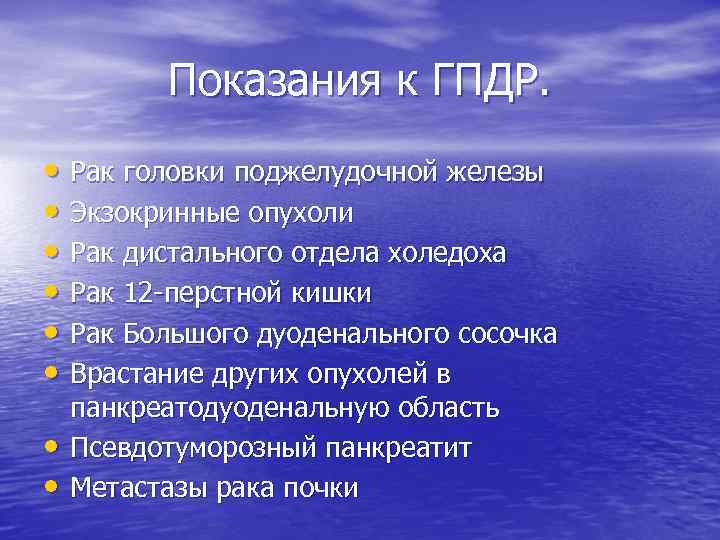

Показания к ГПДР. • Рак головки поджелудочной железы • Экзокринные опухоли • Рак дистального отдела холедоха • Рак 12 -перстной кишки • Рак Большого дуоденального сосочка • Врастание других опухолей в • • панкреатодуоденальную область Псевдотуморозный панкреатит Метастазы рака почки